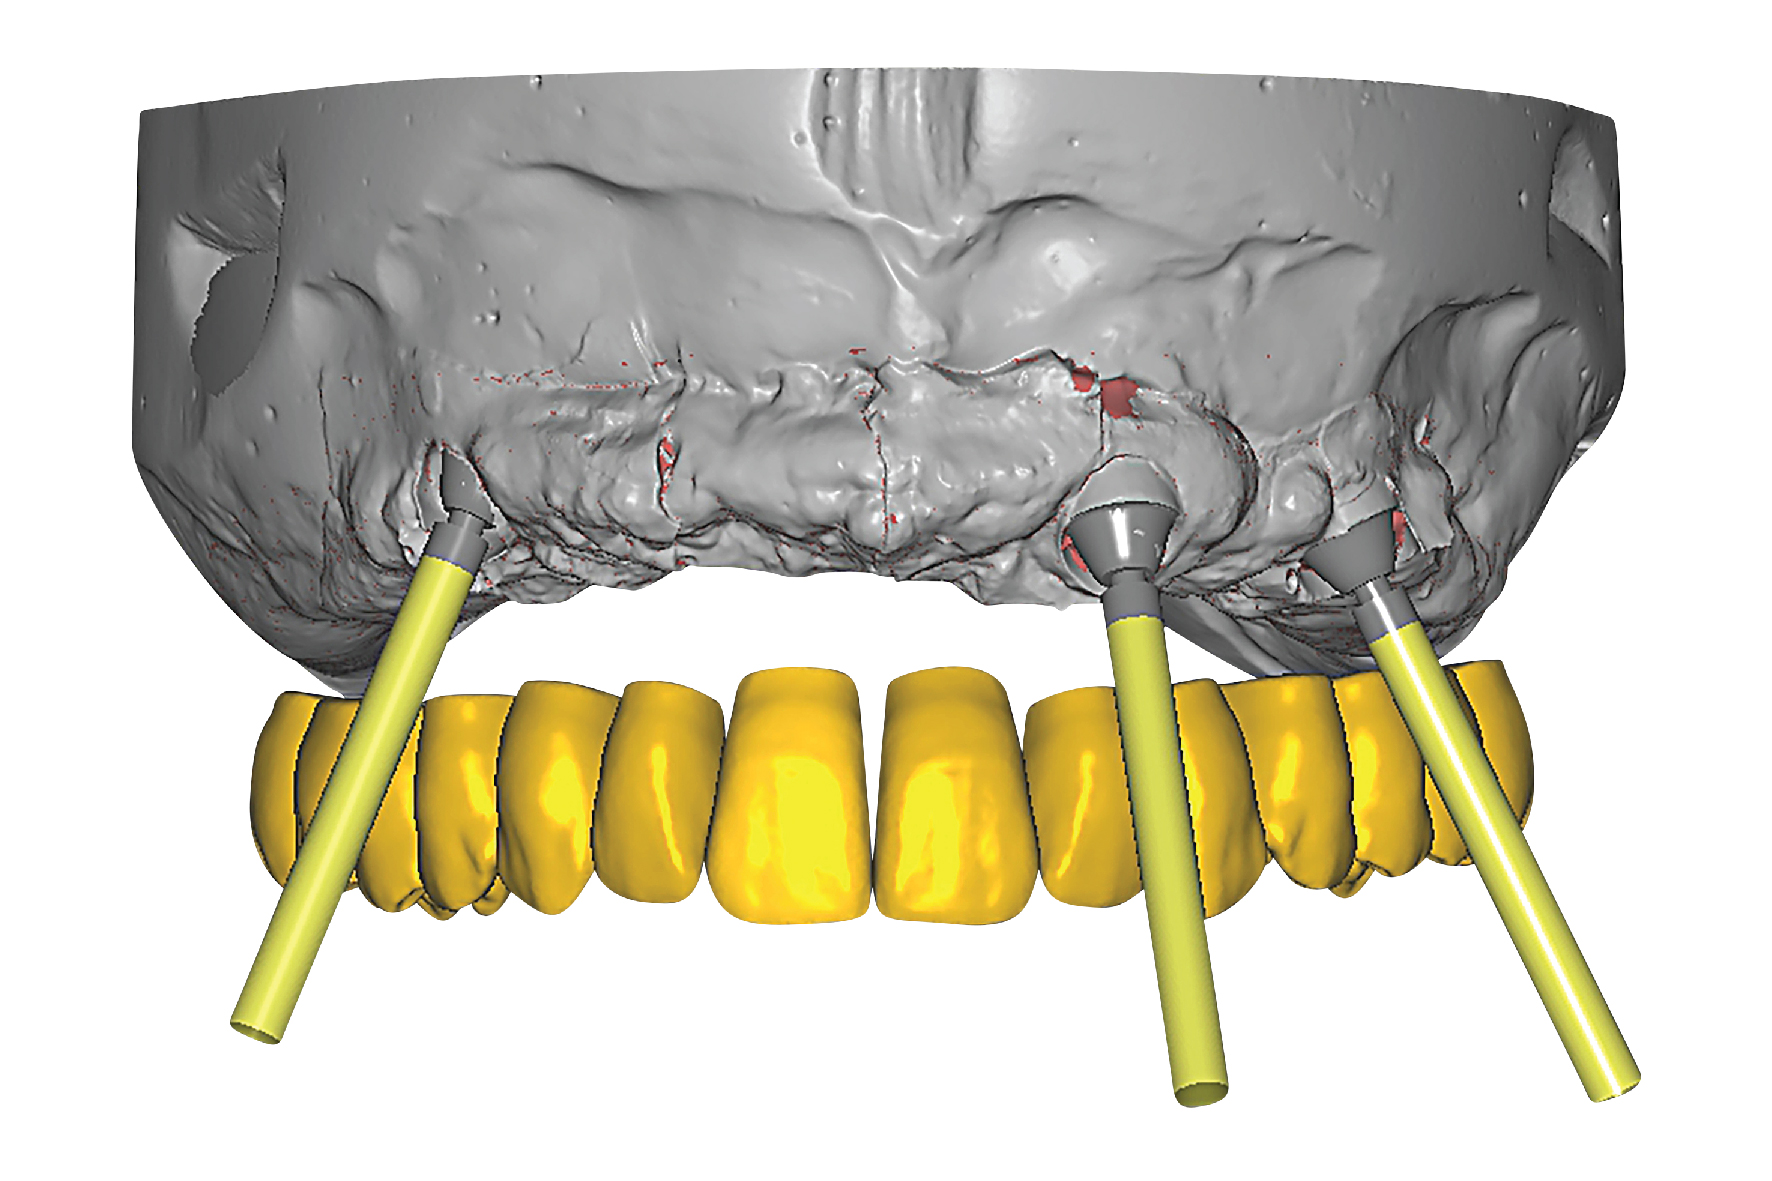

This implant supported bridge offers life changing results and it is bound to exceed your expectations. Supported on as few as four implants, this therapy offers a non-porous, long lasting fixed bridge and is a permanent solution for patients who are frustrated with their current dentures or experiencing significant tooth loss and failing teeth. Since bone loss occurs anteriorly, this amazing prosthesis minimizes bone loss while maximizing esthetics and function. Give your patients the sensation of natural teeth again and the ability to eat what they want rather than what they can! Most patients wonder why they haven’t started treatment sooner and waited so long after experiencing this life changing smile.